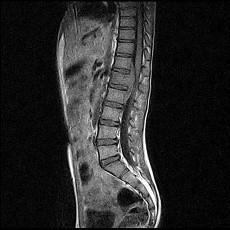

问题 女,9岁,背部隐痛,发热1个月余,MRI检查如图,请选出最可能的诊断 ( )

选项 A、脊椎结核伴硬膜外脓肿 B、椎体压缩骨折 C、脊柱转移瘤 D、硬膜下血肿 E、化脓性脊柱炎

答案 A